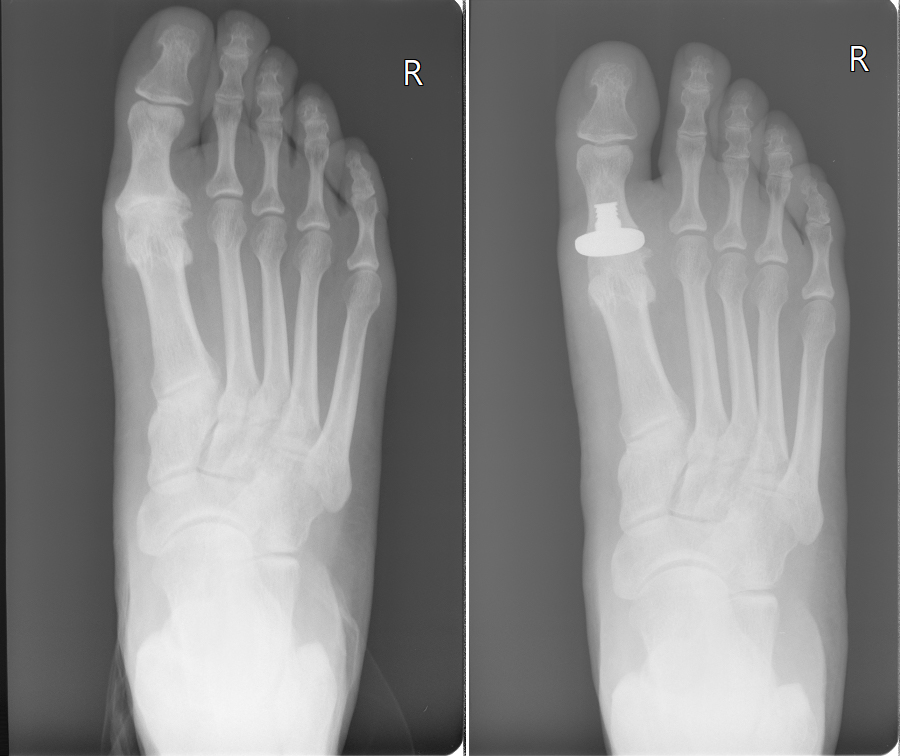

A bunion is a structural deformity in the foot that causes a bony bump to form at the base of the big toe joint. While there are conservative treatments that can slow the progression of a bunion, surgery is the only way to "fix" the deformity.. Research shows that 33% of patients who have undergone traditional bunion surgery are left dissatisfied.. Bunions are a common but painful deformity; however it symptoms might not show up in their early stage of formation. Bunions' symptoms are more noticeable when the deformity gets worst, with some types of shoes and during certain activity, like walking. Some of the symptoms include: A red swelling bump around the big toe joint.